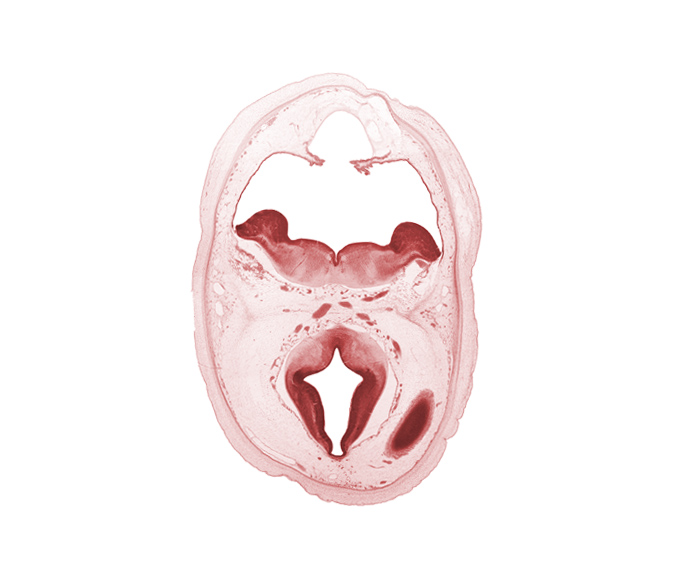

Carnegie Embryo #462 | Location: 1-03-01

Keywords: alar plate of metencephalon (cerebellum), artifact separation(s), basal plate, cephalic end of basilar artery, choroid fissure, diverticulum of rhombencoel (fourth ventricle), dorsal thalamus, hypothalamic sulcus, marginal zone of cerebral vesicle, median sulcus, oculomotor nerve (CN III), posterior communicating artery, rhombencoel (fourth ventricle), rhombic lip, roof plate, sulcus limitans, trochlear nerve (CN IV)

Source: The Virtual Human Embryo.